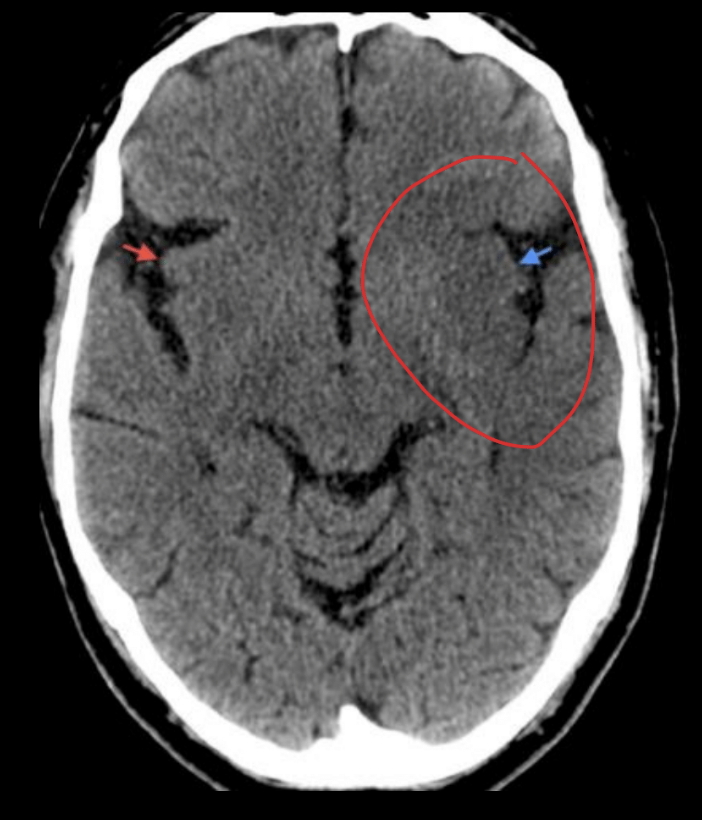

¿Qué fase es? ¿Qué signo ves?

Fase aguda, efecto de masa

Datos de imagen importantes en la fase aguda

Se borran los surcos y giros por “efecto de masa” causado por el edema